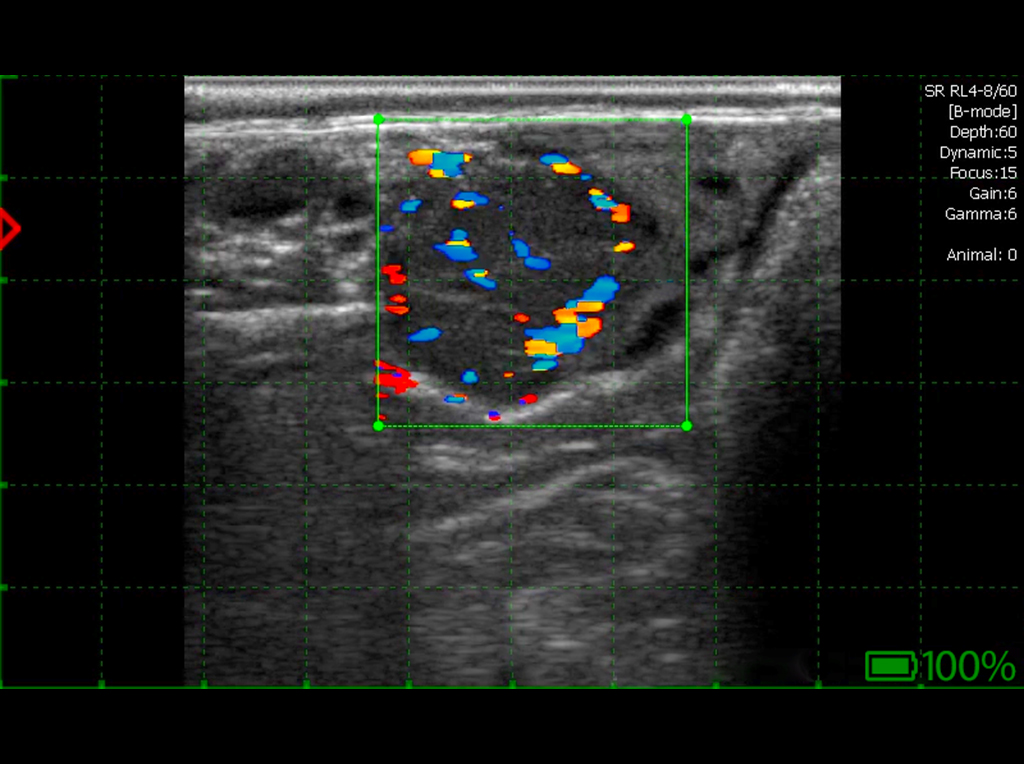

Quiste luteínico en el ovario, espesor de pared superior a 3 mm. Tejido luteínico presente en la pared con flujos Doppler.

Quiste luteínico: pared gruesa con flujos Doppler.